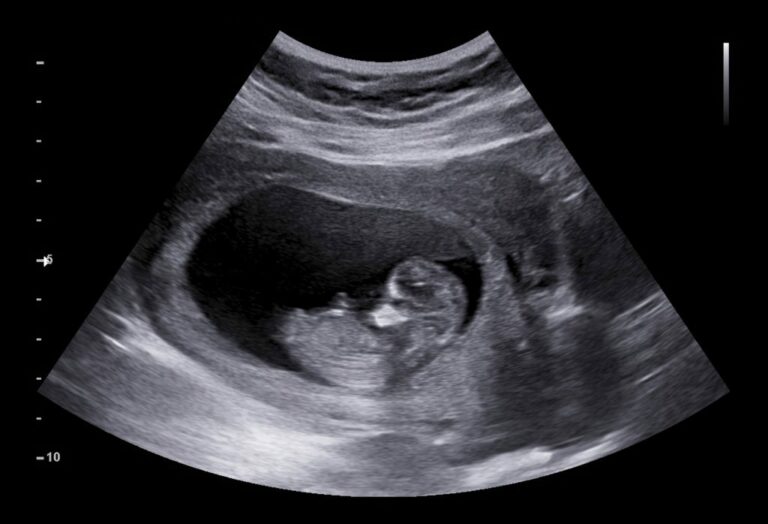

Një video që po shpërndahet në rrjetet sociale shqipfolëse pretendon se tregon pamje ekografike të një fetusi gjatë një aborti. E drejta e abortit është kthyer në një çështje politike gjatë fushatës presidenciale në ShBA me demokratët që mbështesin lehtësimin e politikave mjekësore dhe republikanët më konservatorë.

Me anë të motorit të kërkimit pamor Google Lens, Faktoje gjeti se ajo është shkëputur nga një film i vitit 2019 i quajtur Unplanned.

Jen Villavicencio, një obstetër-gjinekologe që kryen aborte në Michigan, tha për The Huffington Post se skena është “ekstremisht joreale”, pasi fetuset nuk bëjnë lëvizje të vullnetshme në atë fazë të shtatzënisë. “Ideja se një fetus do të tërhiqej ose do të shfaqte frikë ose do të përpiqej të shpëtonte nga një kanulë është një besim i rremë,” tha ajo, duke shtuar se “të gjitha provat thonë se nuk është e mundur”.

Këto imazhe grafike dhe ideja se një fetus mund të ndjejë dhimbje gjatë një aborti janë krejtësisht të pasakta, thotë edhe Katherine McHugh, një anëtare e bordit të Mjekët për Shëndetin Riprodhues dhe një obstetër-gjinekologe në Indiana që kryen procedurat e abortit.

Shumica e ekspertëve mjekësorë pohojnë se një fetus 13 javësh është i paaftë për funksionin kognitiv.

“Ajo që dimë për sistemin neurologjik të një fetusi është se sigurisht në javën e 13-të, nuk ka aftësi për të ndjerë dhimbje,” thotë Dr. McHugh. “Kjo thjesht nuk ekziston ende sepse ajo pjesë e trurit nuk ekziston në këtë moshë gjestacionale. Neuronet që kërkohen për të ndjerë dhimbjen nuk ekzistojnë.” Kjo nuk ndodh deri në tremujorin e tretë, pas 20 javësh, thotë ajo. “Nuk është e saktë të thuhet se një fetus do të tërhiqej ose do të luftonte një sondë ose një thithje,” thotë Dr. McHugh. “Nuk ka asnjë funksion të lartë kognitiv në javën e 13-të; nuk ka aftësi për të ndjerë dhimbje, kështu që nuk ka asnjë refleks.

Sipas Kolegjit Amerikan të Obstetër-Gjinekologëve, një fetus nuk ka aftësinë fiziologjike për të perceptuar dhimbjen deri në javën e 24-të të shtatzënisë.